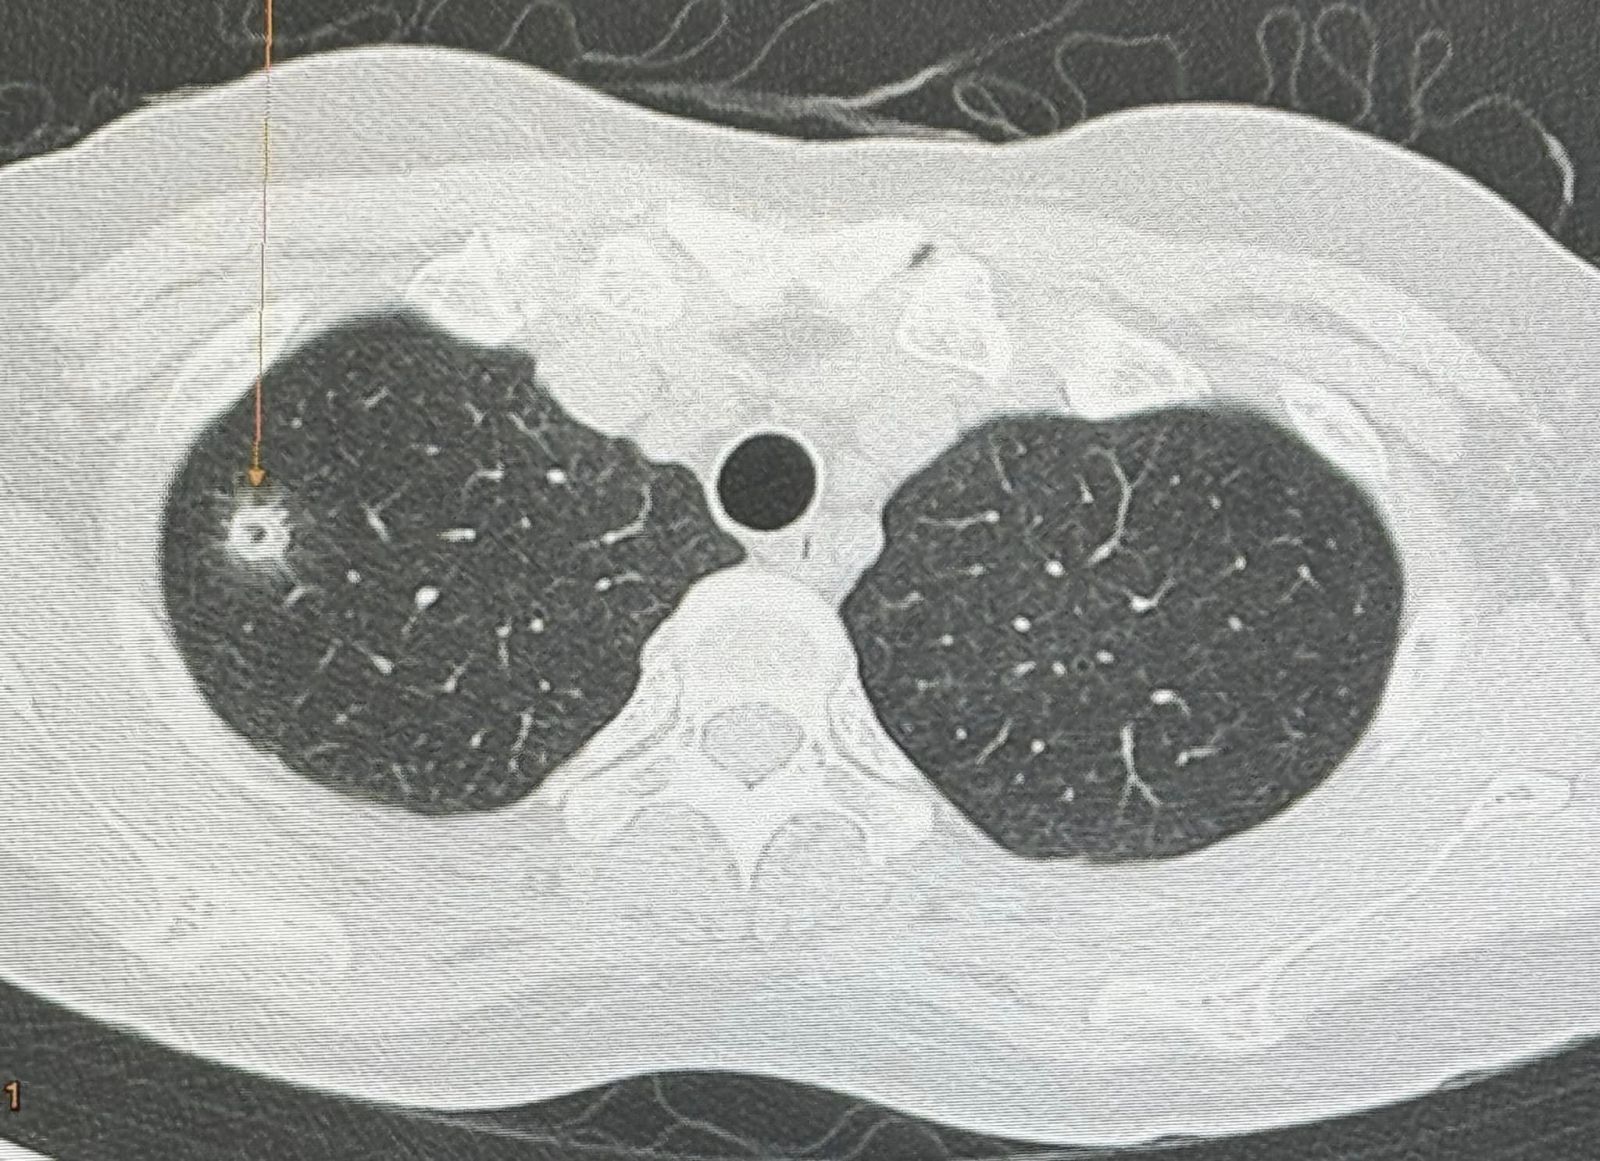

3 มิ.ย. 2567 นพ.มนูญ ลีเชวงวงศ์ ผู้เชี่ยวชาญด้านโรคระบบทางเดินหายใจ ได้โพสต์เฟซบุ๊กระบุว่า "ผู้ป่วยหญิงอายุ 52 ปี บ้านอยู่ กทม. ปกติแข็งแรงดี ไม่ไอ ไม่มีไข้ ไม่เบื่ออาหาร น้ำหนักไม่ลด ไม่ปวดหัว ไม่เคยสูบบุหรี่ ไม่มีโรคประจำตัว ไปตรวจร่างกายประจำปี วันที่ 12 พฤษภาคม 2567 เอกซเรย์ปอดพบก้อนเล็กๆเกิดขึ้นใหม่ที่ปอดขวากลีบบน เอกซเรย์ปอดก่อนหน้านั้น 1 ปีปกติ ทำคอมพิวเตอร์ปอดพบก้อนขนาด 0.9 × 0.9 × 1.7 เซนติเมตร เห็นโพรงอยู่ข้างในก้อนที่ปอดขวากลีบบน ตรวจเลือดไม่ติดเชื้อเอชไอวี ผู้ป่วยไปรับการผ่าตัดปอดเอาก้อนจากปอดขวากลีบบนออกที่โรงพยาบาลใกล้บ้านเมื่อวันที่ 22 พฤษภาคมเพราะสงสัยมะเร็งปอด ผลพยาธิวิทยาเป็นปอดอักเสบจากเชื้อราคริปโตคอคคัส ตรวจเลือดหาคริปโตคอคคัสแอนติเจนหลังผ่าตัด 4 วันให้ผลบวก titer 1:8 แพทย์เริ่มให้การรักษาด้วยยา fluconazole ผู้ป่วยมาขอคำแนะนำหลังจากนี้ควรทำอย่างไรต่อไป

ซักประวัติ มีนกพิราบอยู่แถวบ้านหลายตัว ให้อาหารนกพิราบประจำ ผู้ป่วยรายนี้หายใจสปอร์ของเชื้อราคริปโตคอคคัส นีโอฟอร์แมนส์ (Cryptococcus Neoformans) จากมูลนกพิราบเข้าไปในปอด ทำให้เกิดปอดอักเสบเป็นก้อนที่มีโพรงข้างใน โชคดีที่เชื้อราไม่ได้กระจายออกนอกปอดเนื่องจากร่างกายแข็งแรง มีภูมิคุ้มกันดี วางแผนให้ยาฆ่าเชื้อราฟลูโคนาโซลชนิดกินต่อไปประมาณ 6 เดือน แนะนำให้อยู่ห่าง และหลีกเลี่ยงให้อาหารนกพิราบ"